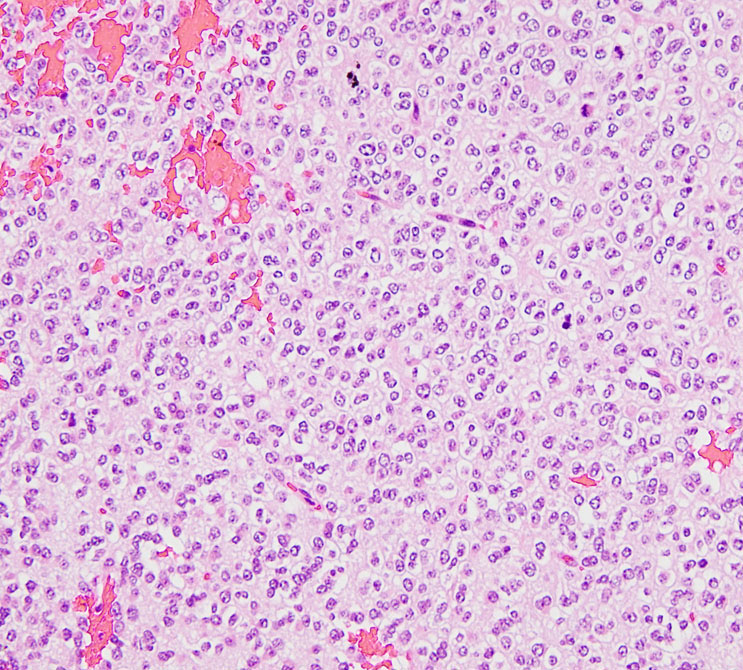

病理所見では,典型的な小さな円形核とその周囲が抜けてみえる perinuclear hallo (fried egg appearance)と細血管の chicken wire appearanceが見られます。

HE染色では,perinuclear haloをもった小型の腫瘍細胞が見られ,また右ではminigemistcyteと呼ばれる小さいけれどeoginophiricな胞体の豊かな腫瘍細胞の出現があり,典型的な乏突起膠腫の像です。

病理像です。左側の部分はperinuclear hallowが多い典型的な乏突起膠腫です。右側の部分ではびまん性星細胞腫の像ですが,その中に乏突起膠腫に特徴的なchicken wireと呼ばれる細い血管網も見られます。乏突起星細胞腫と呼ばれるのですが、腫瘍性格は乏突起膠腫と同じもので,星細胞系腫瘍には入りません。1p/19q欠失があるもののIDH変異がないのでoligoastrocytoma, NOSです。